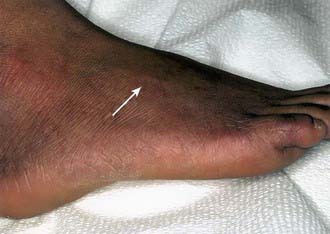

In the borderline tuberculoid (BT) pattern, the lesions are greater in number but smaller in size than in TT. There may be small satellite lesions around older lesions, and the margins of the BT lesions are less distinct. There is usually thickening of 2 or more superficial nerves (Fig. 208-2).

image

Figure 208-2 Thickened, superficial peroneal nerve of leprosy.